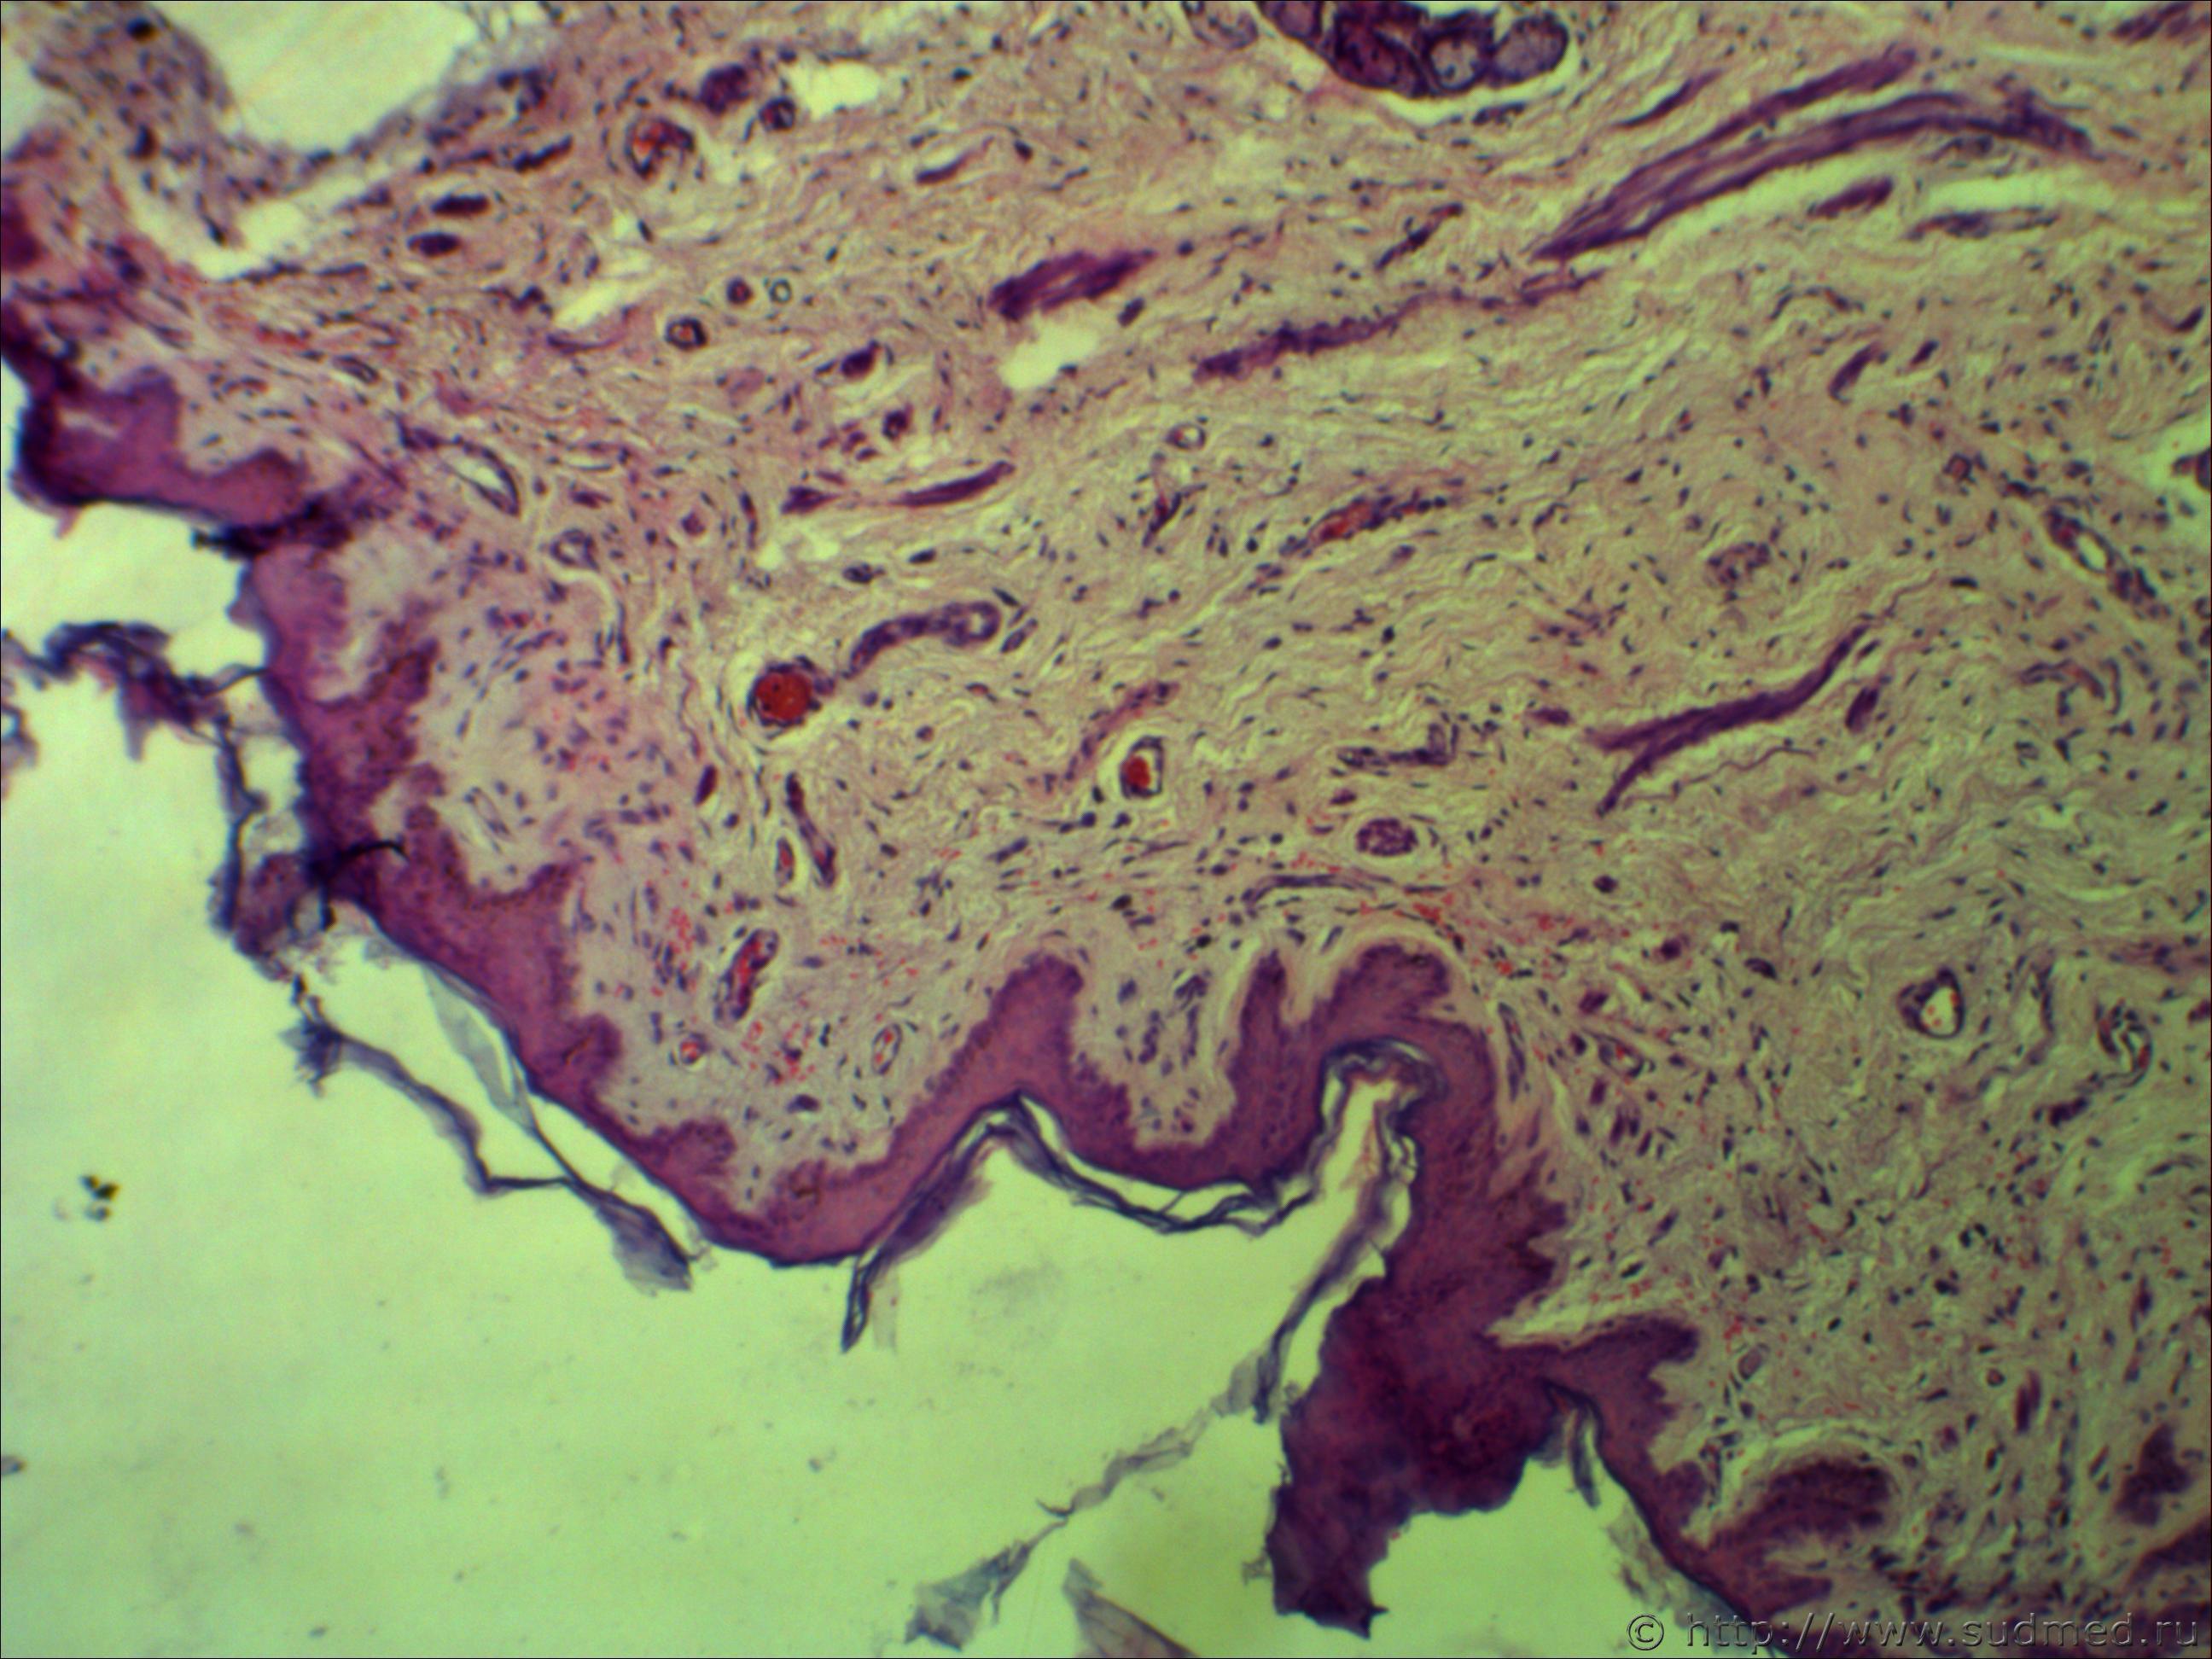

Н/о молочной железы

Похоже на беспигментную меланому.

Нужно показать переход от сохранившей ткани к опухолевой. Старайтесь установить четкости рисунка.

Похоже на грибовидный микоз, либо на лимфоцитому(это мое мнение). В базальных клетках эпидермиса (на малом увеличении, где эпидермис четко ограничен)все таки меланомные пигменты видны, но без нарушения. Но видите как то резкости нет на фото.